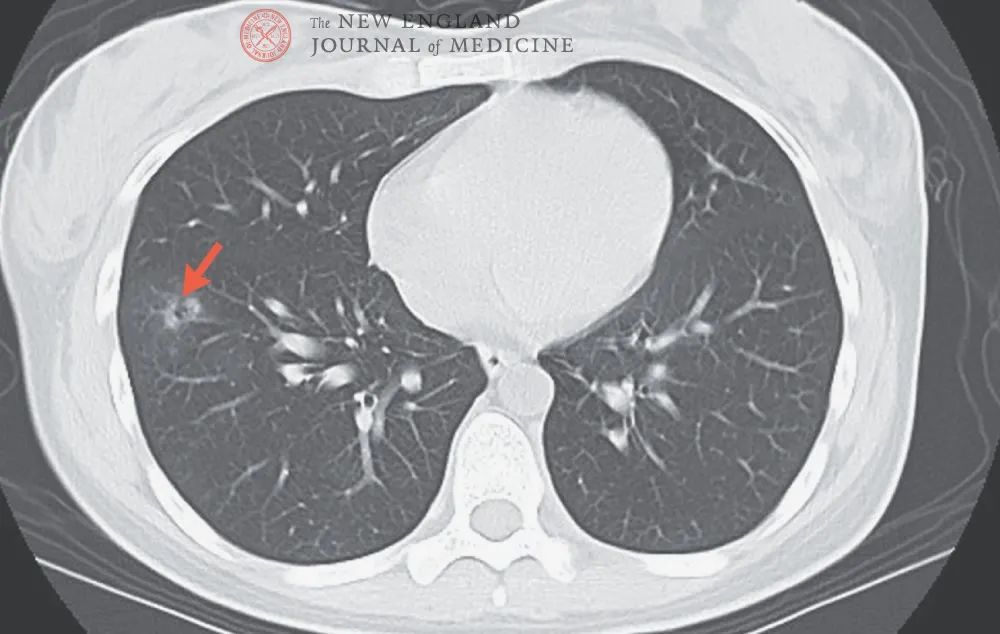

混合磨玻璃结节,伴有胸膜牵拉——肺腺癌